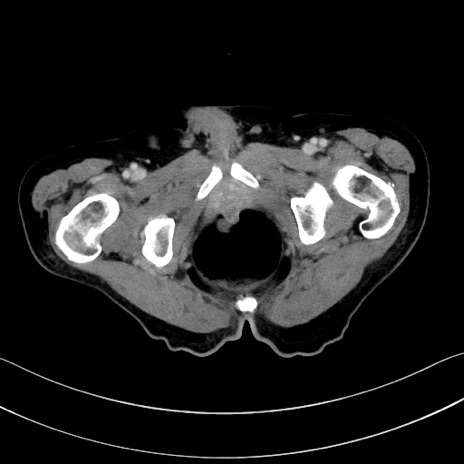

症例28(横断像)

【症例】60歳代男性

【主訴】嘔吐

【現病歴】胃癌にて胃全摘後。食思不振が悪化し、夜中に嘔吐することがある。

【既往歴】胃癌、胃全摘、脾摘、胆摘後

【データ】WBC 5900、CRP 10.56